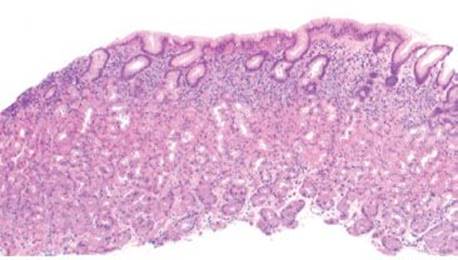

BASAL LYMPHOCYTIC INFILTRATE SUBPATTERN

This subpattern of chronic gastritis is defined by a low-lying lymphocytic infiltrate that expands the lamina propria between the base of the gastric glands and the muscularis mucosae. The prototypical case shows a “band-like” infiltrate hugging the muscularis mucosae at scanning magnification. High-power examination shows admixed plasma cells and occasional eosinophils, but the dominant cell type is lymphocytes (Figs. 2.79, 2.97 and 2.98).

Compartment, Basal Lymphocytic Infiltrate Subpattern

Recognizing the compartment in which this pattern arises can aid in determining the etiology of the chronic gastritis. For example, when found isolated to the gastric body/fundus, the changes are more likely related to AMAG, and further identification of additional AMAG patterns of injury can be helpful. In contrast, involvement limited to the antrum (or mixed antral and oxyntic involvement) suggests the etiology may be related to EMAG; however, identification of other concurrent patterns of injury is necessary.